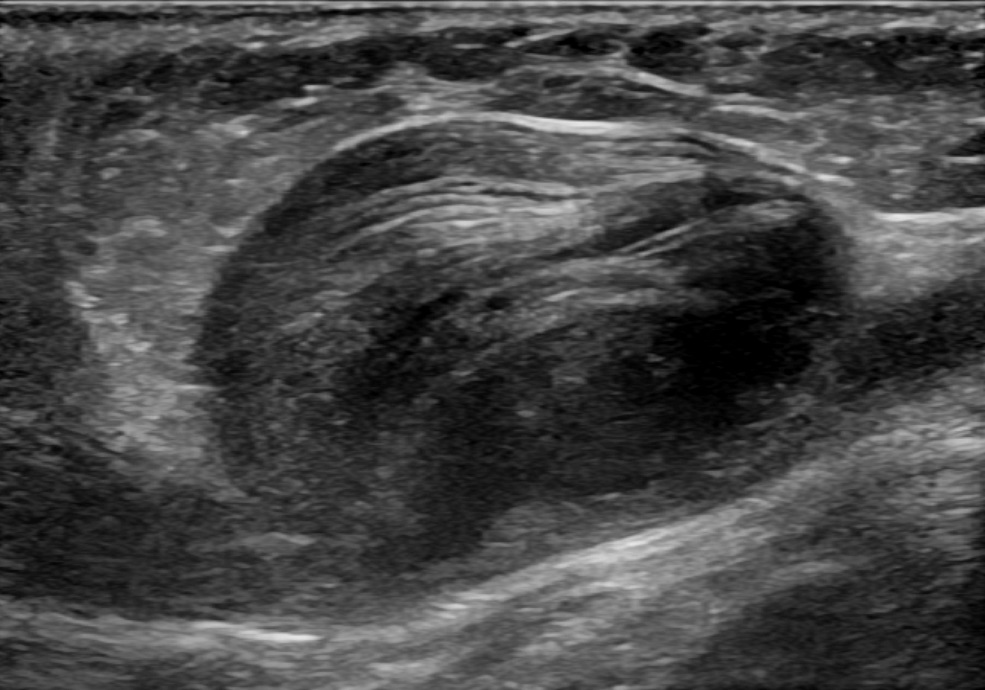

진성 동맥류는 동맥벽의 세 층(내막, 중막, 외막) 모두를 포함하는 동맥류이다. 진성 동맥류에는 죽상경화성 동맥류, 매독성 동맥류, 선천성 동맥류뿐만 아니라 관통성 심근 경색 후 발생하는 심실 동맥류도 포함된다(심장벽의 모든 층을 포함하는 동맥류도 진성 동맥류로 간주된다).[3]가성 동맥류(위동맥류)는 동맥 또는 정맥에서 완전히 새어나온 혈액이 주변 조직에 의해 혈관 옆에 국한된 것이다. 이 혈액으로 채워진 공동은 결국 누출을 봉쇄할 만큼 혈전(응고)되거나 주변 조직에서 파열될 것이다.[3]

위동맥류는 칼이나 총상과 같은 동맥에 구멍을 뚫는 외상[4], 관상 동맥 조영술이나 동맥 이식과 같은 경피적 수술 절차[5], 또는 주입을 위한 동맥 사용[6]의 결과로 발생할 수 있다.